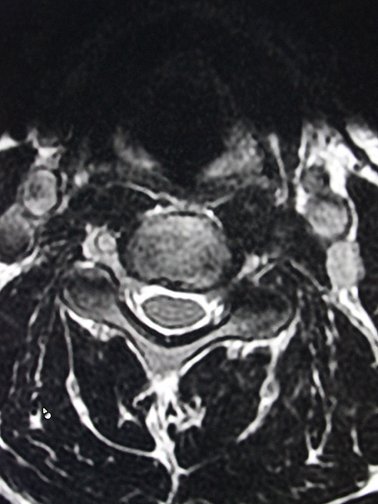

Bei der Kernspintomografie werden Schnittbilder des Körpers mittels eines starken Magneten (1,5 Tesla) und bestimmter Hochfrequenz-Spulen angefertigt. Diese Untersuchung hat keinerlei Strahlenbelastung. Es handelt sich um eine Magnetröhre die beidseits offen ist. Die Bilder ergeben einen hervorragenden Weichteilkontrast, so dass diese Untersuchungsmethode insbesondere für das Zentralnervensystem, die Wirbelsäule sowie Gelenke und den Bauchraum geeignet ist. Auch die Darstellung der Gallenwege und der Gefäße ist in der MRT möglich. Bei einem Teil der Untersuchungen ist ein Kontrastmittel notwendig. Dies wird intravenös gegeben.

Für Privatversicherte und Selbstzahler bieten wir eine Ganzkörper-MRT Untersuchung an, um in c.a. 45 Minuten alle Organe von Kopf bis Fuss "screenen“ zu können, ob etwas Krankhaftes vorliegt. Diese Untersuchung kann Krankheiten oder Tumore erkennen, bevor diese bemerkt werden.